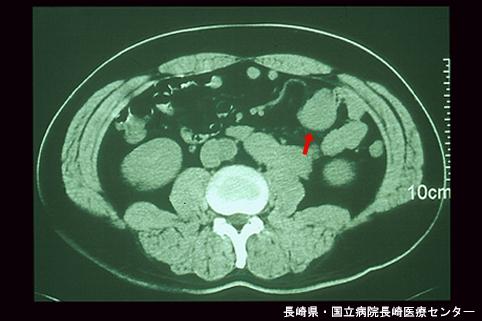

症例提示(所在地,施設名等): 長崎県・ 長崎医療センター

疾患(病理主体)の分類悪性非上皮性腫瘍/平滑筋肉腫(含GIST)

部位(臓器別)小腸/空腸

検査方法CT

病変の最大径(ミリ)40以上

腫瘍の深達度mp